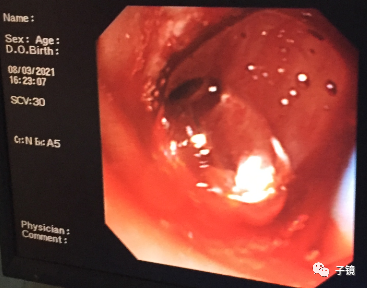

加力往下拖,看到数个不完整的黄色碎石出来了,应该是结石给予取石球囊压碎了。

接下来把取石球囊送到胆总管上段,反复注水冲洗胆道,在乳头口吸引出大量胆泥,直至冲洗干净。